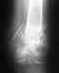

Следует обратить внимание на рентгенограммы таза, которые не представлены. Уместно сделать и компьтерную томографию.

О том и речь, что поскольку таз - кольцо, при наличии перелома в передней части вероятно повреждение таза и в задних отделах.

обязательно предоставлю снимок рентгента(его можно отсканировать?????) снимок делался так-я лежал на спине,аппарат сверху.......может тоже надо мне 27, рост 176, вес на момент аварии 100, сейчас 103